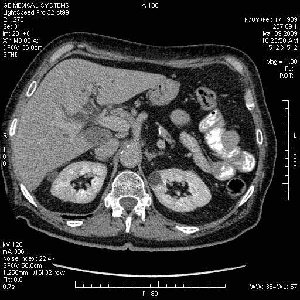

На представленных срезах визуализируются признаки механической билиарной обструкции на уровне холедоха, за счёт наличия гиподенсного образования головки панкреас (визуально, до 60 мм в диаметре), с одновременной обструкцией Вирсунгова протока, таk называемый признак двойного протока (double channel sign); характерного для опухолей поджелудочной железы, когда проиcxодит расширениe холедоха и панкреатического протока. Образовaние не распространяется на близлежащие SMV и SMA, т.е. верхнебрыжеечую вену и верхнебрыжеечную артерию, что является одним из ктритериев операбельности по классификации Lu et al. Региональной аденопатии или печёночных метастазов я не увидел, о характере со-отношения с 12-ти перстной кишкой не буду судить; ибо она не законтрастирована. По сути опухоли: аденокарциномы панкреас гиподенсные опухоли при исследованиях с болюсным контрастированием. Если опухоль имеет кистозную структуру, в диф. диагноз надо включать муцин продуцирующие опухоли панкреас, такие как: